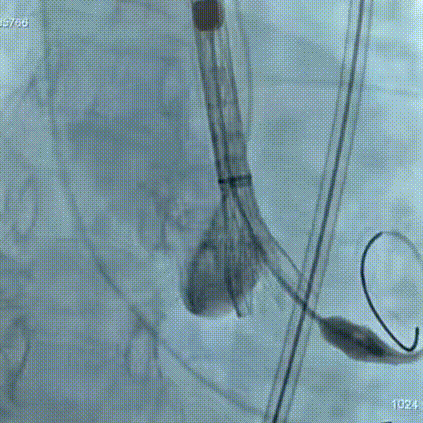

手术过程

手术过程:在右股动脉穿刺建立通路后,顺利送入大鞘,经食道超声及血管造影确认路径稳定。18mm球囊预扩后评估冠脉灌注良好,后将Prostyle A® AV26瓣膜精准释放于目标位置,超声显示无瓣周漏,术后即刻造影显示无明显反流,术前PGmean40mmHg,术后导管测平均跨瓣压差8mmHg,心功能明显改善,患者生命体征平稳。

主动脉根部造影

定位

迅速锚定